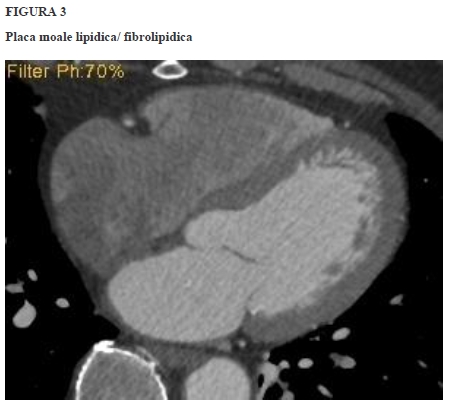

Sub acest auspiciu, conceptul de „placa vulnerabilă” a devenit relevant. Au fost identificate 4 prototipuri morfo-histologice asociate riscului înalt de declanșare a MACE. Plăcile aterosclerotice coronariene susceptibile la ruptură au morfologie distinctă, în comparație cu cele stabile. În linii mari, cele patru morfotipuri, stabilite ca atare prin corelație cu IVUS și cu aspectul histo-patologic, sunt descrise ca și:

■ placă voluminoasă cu structura predominant lipidică, localizată la limita intimă-medie a arterei, fără îngustare semnificativă a lumenului subiacent; asociază sau nu „dilatarea” arterei prin remodelarea pozitivă a peretelui,

■ depozit cu structură moale, predominant lipidică, dar delimitat prin lizereu („capișon”) fibros,

■ placă degradată în porțiunea centrală prin hemoragie/necroză (napkin-ring sign),

■ microcalcificări (spotty calcification) în placa lipidică/ fibrolipidică.

În cazul plăcilor vulnerabile, riscul de MACE nu se corelează fidel cu gradul stenozei, ci cu predispoziția la eroziune, ruptură, tromboză. De aici importanța identificării precoce a plăcii cu risc, iar singura metodă imagistică neinvazivă relevantă în evidențierea, caracterizarea și încadrarea morfo-structurală a plăcii vulnerabile este considerată, în prezent, angio-coronarografia CT.

Spre exemplificare, iată câteva imagini de coronarografie CT, în care sunt prezentate morfotopurile de plăci de aterom vulnerabile.